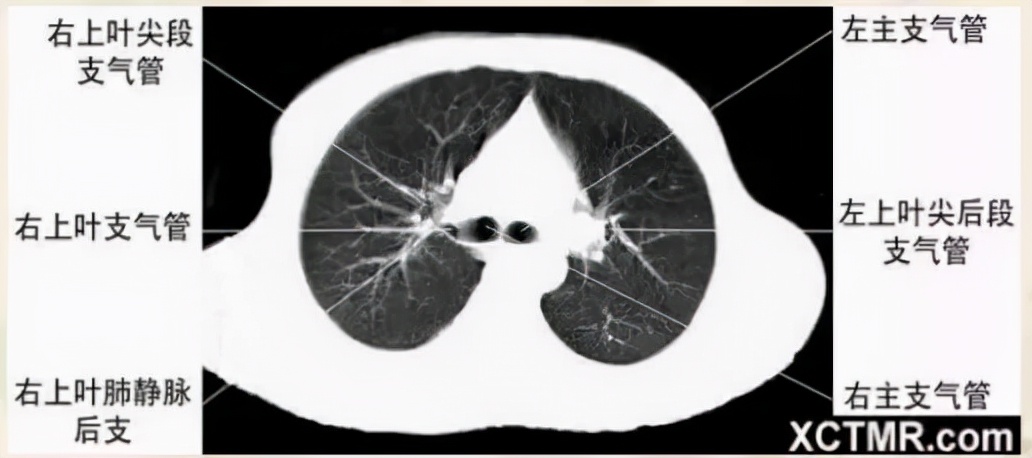

气管分叉层面